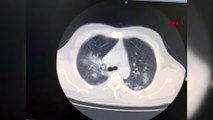

Koronavirüs akciğerinin yüzde 70'ini kaplamıştı, koronavirüsü yenen doktor anlattıGökçe KARAKÖSE / İSTANBUL, (DHA)- Yoğun kas ağrısı şikayeti olan İç Hastalıkları Uzmanı Celal Civil, akciğer tomografisinin ardından koronavirüse yakalandığını fark etti.

Gökçe KARAKÖSE / İSTANBUL, (DHA)- Yoğun kas ağrısı şikayeti olan İç Hastalıkları Uzmanı Celal Civil, akciğer tomografisinin ardından koronavirüse yakalandığını fark etti. 8 gün evde tedavi gören Civil'in durumu kötüye gitmeye başladı. İkinci tomografisinde koronavirüsün akciğerinin yüzde 70'ini kapladığı görülen genç doktor, yaklaşık 1 aylık tedavisinin ardından sağlığına kavuşarak görevine döndü.